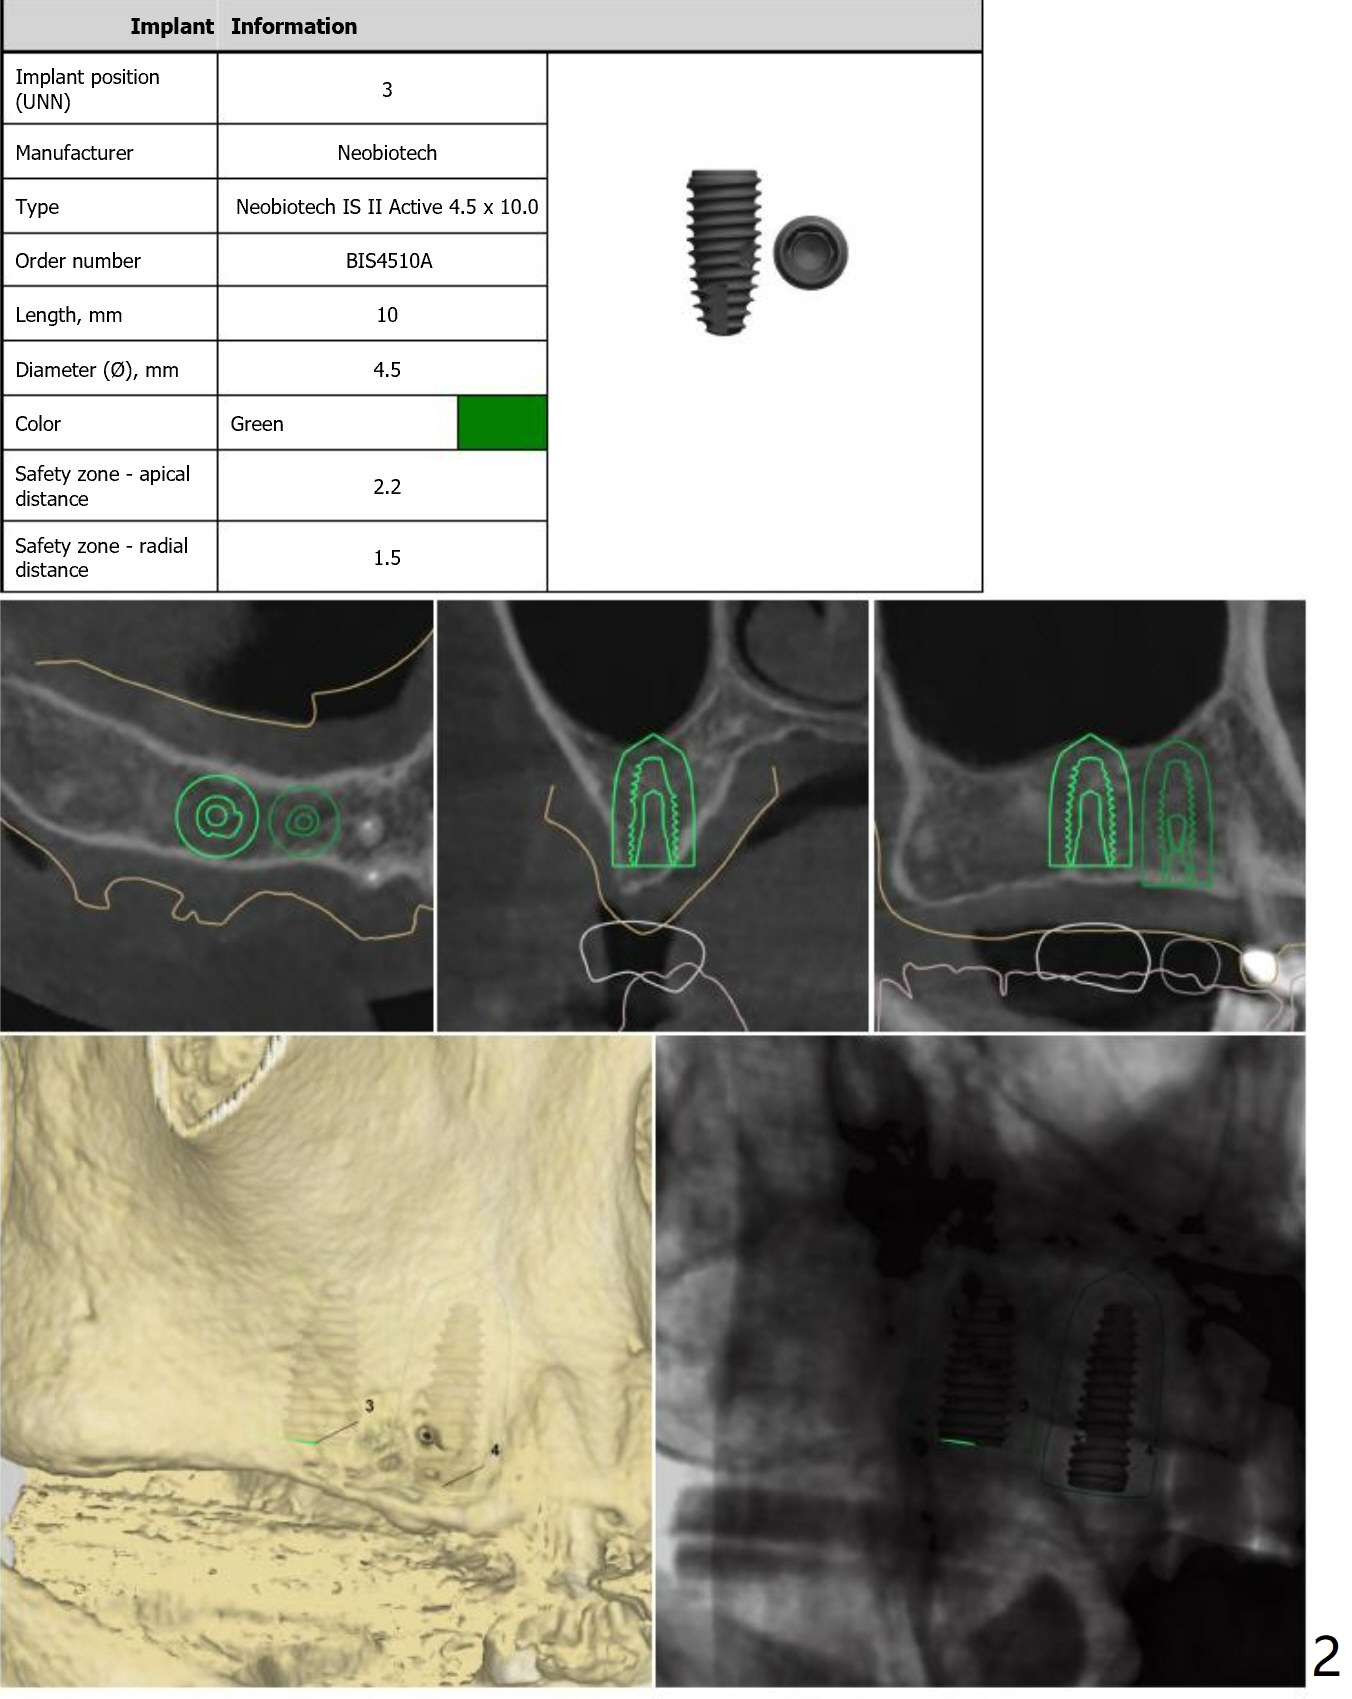

No Tap

Return to Upper Molar Premolar Immediate Implant, Trajectory